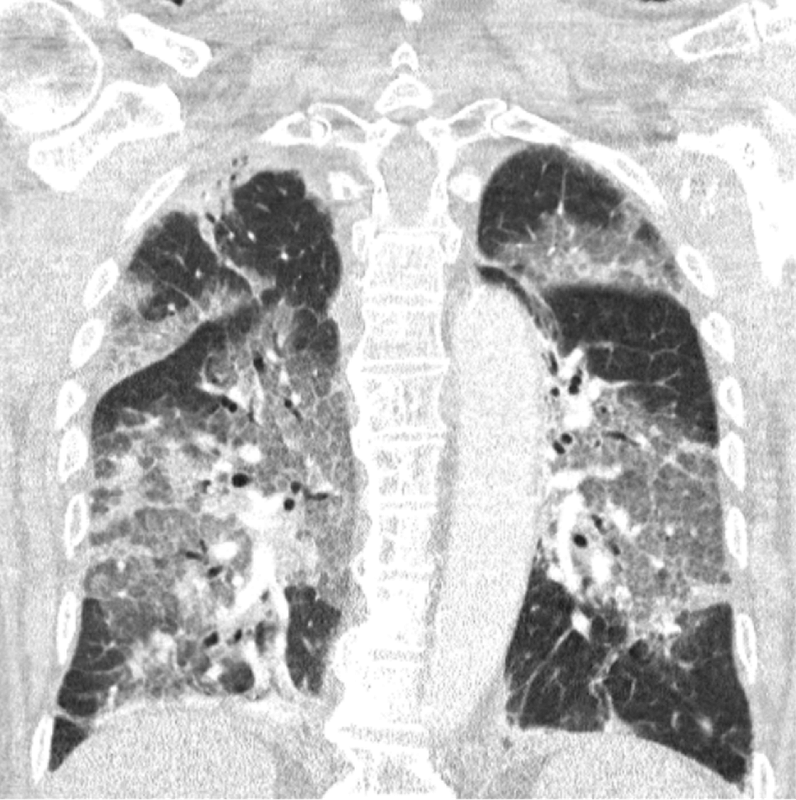

https://www.zuyderland.nl...pen-brief-van-zuyderland/

Vandaag namen wij de eerste patiënt op in ons ziekenhuis die het Astra-Zeneca-vaccin had geweigerd na alle commotie in de pers. We hoorden de enorme spijt in zijn stem en zagen de wanhoop in zijn ogen. Het virus had hem geveld en dit had wellicht niet gehoeven. Met zijn instemming delen wij hier zijn longscan. Je hoeft geen longarts te zijn om de verwoestingen te herkennen. Je hoeft ook geen epidemioloog te zijn om de risico’s van niet-vaccineren te duiden. Het risico op ernstige schade door COVID-19 is tien keer hoger voor 40 jarigen, en zeventig keer voor 60 jarigen, dan het risico op ernstige schade door trombose als gevolg van het vaccin.

Al ruim een jaar trekken wij in Zuyderland elke dag ten strijde tegen het virus. Daarnaast zetten we ons in voor al die andere patiënten met kanker of andere ziekten. We hebben nu ruim 3000 coronapatiënten in zorg gehad, en terwijl u met de experts discussieert over het stapsgewijs heropenen van de samenleving om perspectief te bieden, zien wij nog elke dag de enorme gevolgen van deze ziekte. Niet alleen onze patiënten, ook onze medewerkers worden getroffen door de pandemie. Regelmatig worden collega’s ziek, raken uitgeput en niet zelden volledig arbeidsongeschiktheid. Dagelijks leggen onze medisch specialisten aan al hun patiënten uit dat vaccineren écht belangrijk en écht veilig is. Zo hopen ze bij te dragen aan het creëren van vertrouwen en tegenwicht te bieden aan alle verwarring in de pers. Wij hebben dan ook met verbijstering kennisgenomen van de politieke besluitvorming rond de vaccins van Astra Zeneca en Janssen.

Beste minister, wij kunnen niet langer wachten. Geen dag langer. Onze IC’s liggen vol met dertigers, veertigers en vijftigers. Door ziekteverzuim en uitputting krijgen we de planning niet meer rond. Medewerkers stellen de terechte vraag waarom zij zorg moeten blijven leveren zonder adequate bescherming, en dat terwijl de vaccins liggen te wachten in de koelkast. Gisteren in het nieuws: ‘Opschalen tot 1550 IC-bedden gaat waarschijnlijk niet lukken’. Wij vergaderen dagelijks over hoe we code-zwart kunnen voorkomen. Elke dag langer wachten betekent voor ons dat het moeilijker en moeilijker wordt om de gevraagde zorg te leveren en de moraal hoog te houden. En dan hebben we het nog niet gehad over de ruim 5000 ingrepen die nog ingehaald moeten worden in ons ziekenhuis. Ingrepen bij patiënten met borstkanker en darmkanker die uitgesteld worden omdat onze IC’s vol liggen.

Wilt u alstublieft stoppen met dralen en onrust zaaien, met insinueren dat u veiligheid biedt door alles eerst goed uit te laten zoeken? De cijfers die de voordelen van massavaccinatie aantonen zijn overweldigend. Ze liegen echt niet. Laten we dan landelijk de maximale vaart erin brengen! Laat mensen zelf de keuze of ze een situatie als die waarin onze patiënt is beland, willen vermijden. Laten we er samen voor zorgen dat onze medewerkers naar behoren zijn toegerust om hun uitzonderlijk zware taak kunnen blijven volbrengen door ze nog vandaag te beschermen met een vaccin.

Het is nu tijd om te laten zien dat u daadwerkelijk gelooft in uw zorghelden. Astra-Zeneca, Janssen of welk vaccin dan ook: wij willen prikken in plaats van eindeloos debatteren of het advies van de Gezondheidsraad nu wel of niet deugt. Net zoals een meerderheid van de Tweede Kamer pleiten wij voor vrijwillige vaccinatie op basis van ‘informed consent’. Wij overwegen dan ook serieus om vanaf aanstaande maandag de paar honderd Astra-Zeneca vaccins die nog in de koeling liggen te wachten, aan te bieden aan medewerkers en dokters.

Wij hebben als professionals een zorgplicht jegens patiënten en collega’s. Die zorgplicht weegt zwaar! Niets doen en afwachten leidt tot meer, niet tot minder schade. En aan vermijdbare schade werken wij in Zuyderland niet langer willens en wetens mee.

Namens Zuyderland,

Medisch Specialisten, Chief Nursing Officer en Raad van Bestuur

Afbeeldingslocatie: https://tweakers.net/i/T78Qiew3rkdWx4i9lqYhrPRWhlM=/x800/filters:strip_exif()/f/image/0YHkKgcorHl3a3AIpsGACNlr.png?f=fotoalbum_large